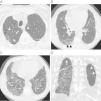

DiagnósticoPruebas de imagenEn la radiografía de tórax simple se puede apreciar un patrón intersticial o infiltrados reticulonodulares de distribución bibasal y periférica (subpleural) e hiperclaridad en los vértices con disminución de la trama vascular a ese nivel (fig. 1). Sin embargo, la radiografía de tórax puede inadvertir los hallazgos radiológicos de la CFPE, siendo la TCAR la exploración de referencia para confirmar el diagnóstico23,45. Las imágenes muestran la presencia de enfisema de predominio en lóbulos superiores, definido por una zona hipodensa bien delimitada sin pared, o con una pared muy fina y/o múltiples bullas, que coexiste con diversas manifestaciones radiológicas propias de las enfermedades difusas del pulmón, como lo son opacidades reticulares, bronquiectasias de tracción, áreas de engrosamiento septal, vidrio deslustrado y panal de abeja en lóbulos inferiores (fig. 2). Las lesiones enfisematosas corresponden a enfisema centrolobulillar y paraseptal (bullas subpleurales). El enfisema paraseptal se ha descrito hasta en una 90% de los casos, por lo que algunos autores sugieren que se trata de un rasgo característico de la CFPE1,23,46.

Radiografía de tórax de un paciente diagnosticado de combinación de fibrosis pulmonar y enfisema. Se observa afectación patrón intersticial bilateral, de predominio derecho con infiltrados reticulonodulares de distribución basal y subpleural y disminución de la densidad pulmonar en campos superiores, principalmente izquierdo.

Tomografía computarizada de alta resolución (TCAR) del mismo paciente. A) Presencia de enfisema paraseptal y bullas subpleurales (cabezas de flecha blancas) y enfisema centrolobulillar (flechas) en ambos lóbulos superiores. B) Afectación intersticial reticular con engrosamiento intralobulillar e imágenes de panalización subpleural y bronquiectasia de tracción (cabezas de flecha negras) C) Afectación intersticial reticular en lóbulo medio y lóbulo inferior derecho , con engrosamiento de septos interlobulillares, panalización subpleural y bronquiectasias por tracción. D) Reconstrucción coronal a nivel de regiones posteriores de ambos pulmones: Enfisema paraseptal bilateral (cabezas de flecha blancas) y afectación intersticial reticular y panalización en lóbulo inferior derecho.